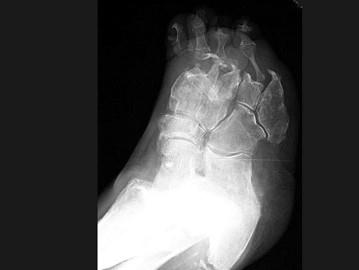

女,78岁,长期慢性手足畸形,无冷热、痛感,结合图像,最可能的诊断是?(?)A.骨麻风病B.骨梅毒C.骨结核D.痛风E.类风湿关节炎

问题 女,78岁,长期慢性手足畸形,无冷热、痛感,结合图像,最可能的诊断是?(?)

选项 A.骨麻风病 B.骨梅毒 C.骨结核 D.痛风 E.类风湿关节炎

答案 A